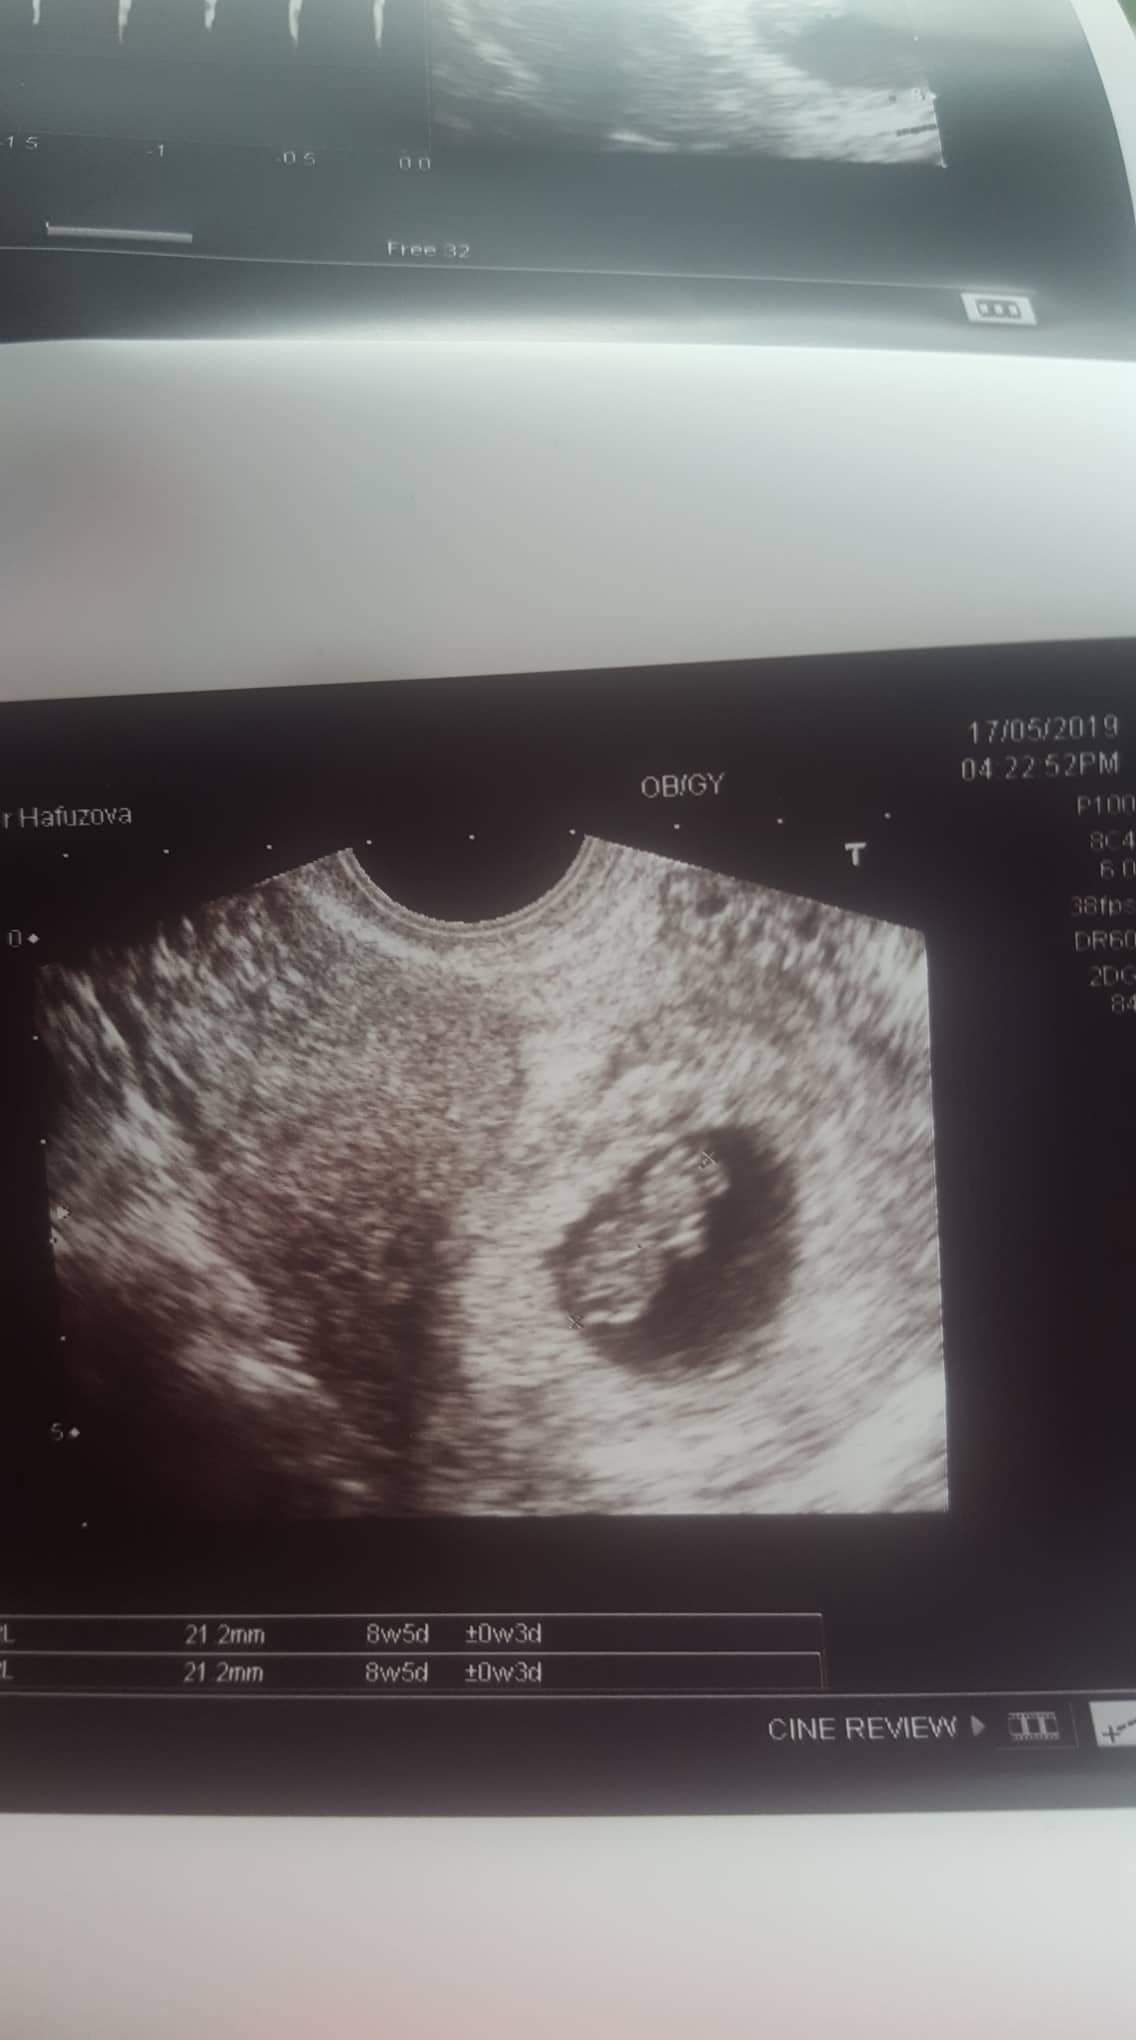

Бебчо е добре 21.2 мм е 8с и 5 ден . Това зацапване пак не знаем откъде е , но каза че няма общо с бебето . То си е добре сърцето биеше много силно  и бързо. Аз съм забременяла от левия яйчник и по от ляво си седи . Ще видим какво ще е на 3 пак съм на преглед и ще изберем дата за феталната и бхс . Решили сме 4д да правим...  Добре Дошли на новите мами  и никакво предаване.  И аз съм една паника обаче цял ден си повтарям , че всичко ще е наред и така ще бъде.  💙